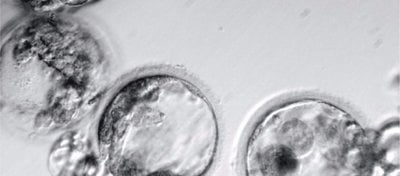

Kök Hücre